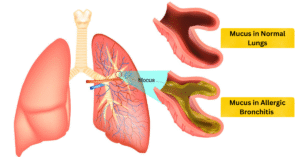

Are you feeling shortness of breath, coughing & wheezing? Allergic Bronchitis is a respiratory condition where allergens trigger inflammation in the bronchial tubes, leading to symptoms like coughing, wheezing, shortness of breath, and chest tightness. In this article, we’ll explore how homoeopathy offers a personalized and comprehensive approach to treating allergic bronchitis, focusing on root cause, symptom relief, and overall well-being through natural remedies and lifestyle changes.

– Excessive mucus production, which may be clear, yellow, or greenish

Allergic bronchitis can be a challenging condition to manage, with symptoms like persistent coughing, wheezing, and shortness of breath affecting daily life. Homoeopathy offers a holistic and personalized way to address allergic bronchitis, focusing on treating the individual rather than just the symptoms. By understanding how homoeopathy works and its benefits, individuals can make informed decisions about their healthcare and find effective ways to manage their condition.